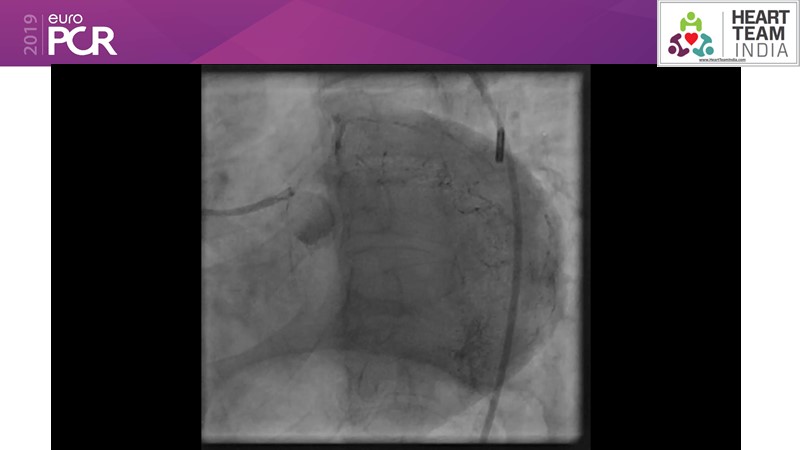

Ability to treat diabetic patients: DES + DCB strategy

Consult this session to get insights about the need for a dedicated drug eluting stent (DES), as well as the benefits of a DES+DCB strategy, for diabetes mellitus (DM) and acute MI (AMI) patients.

- To understand and learn benefits of DES+DCB strategy to provide uniform and homogenous drug delivery in patients with diabetes mellitus and acute MI